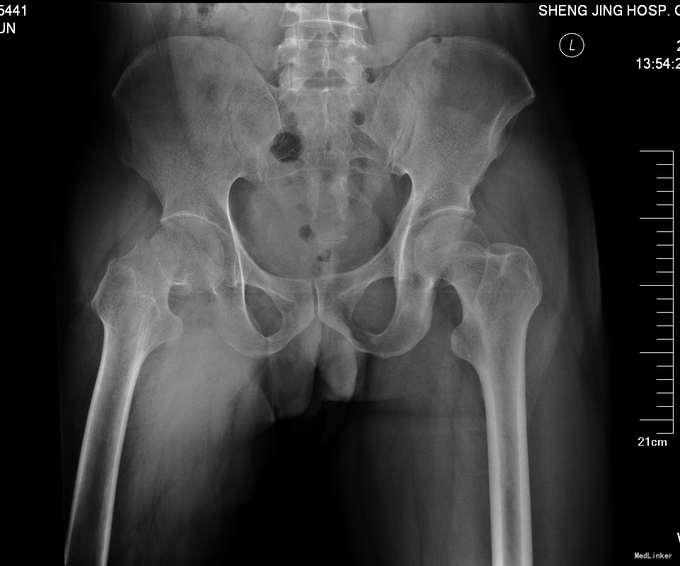

主诉:摔伤后右髋部疼痛活动受限9小时 现病史:患者及家属自述患者于2014年4月24日在中国医科大学附属盛京医院门口被人推倒摔伤,致右下肢疼痛活动受限。被急送至我院急诊就诊。行骨盆DR,右下肢DR检查示:右股骨颈骨折。患者为求系统诊治来我科治疗。患者平车入病房,无发热,无头晕头迷,无胸闷气短,无心慌心悸,无腹痛腹胀,受伤后大便未排,小便正常。

查体右髋部未见明显肿胀及瘀斑,右大腿外旋畸形约45度。右股动脉搏动有力,肢体末梢血运良好,皮温正常。右髋部压痛(+)扣击痛(+)。右髋关节活动受限。